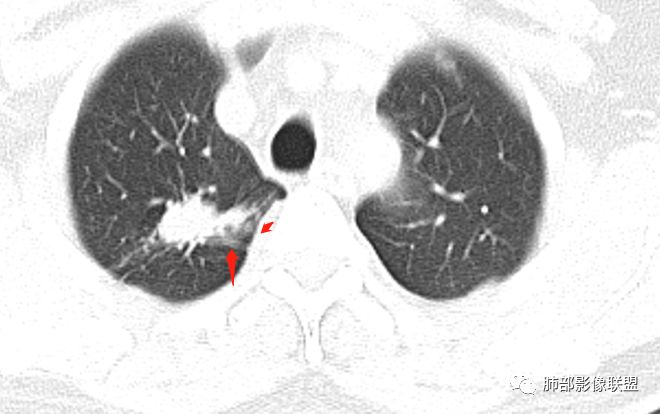

影像,气管憩室,两肺尖都有病灶,长索条

右肺上叶病灶两部分

纵隔窗提示内侧部分密度不够实

边缘平直、凹陷为主,部分膨隆

内部小点状影提示可能支气管腔内粘液栓

左肺尖及右肺病灶附近见小斑点,边界尚清

1、病灶整体形态不是类圆形,边缘凹陷、平直为主,长轴重建可能更明显,长索条,附近卫星灶,左肺尖有类似小高密度影;按常规:首先要考虑结核

南边:2、不踏实的地方:GGO是不是容积效应所致?如果薄层,边界清楚GGO,就考虑继发瘢痕癌